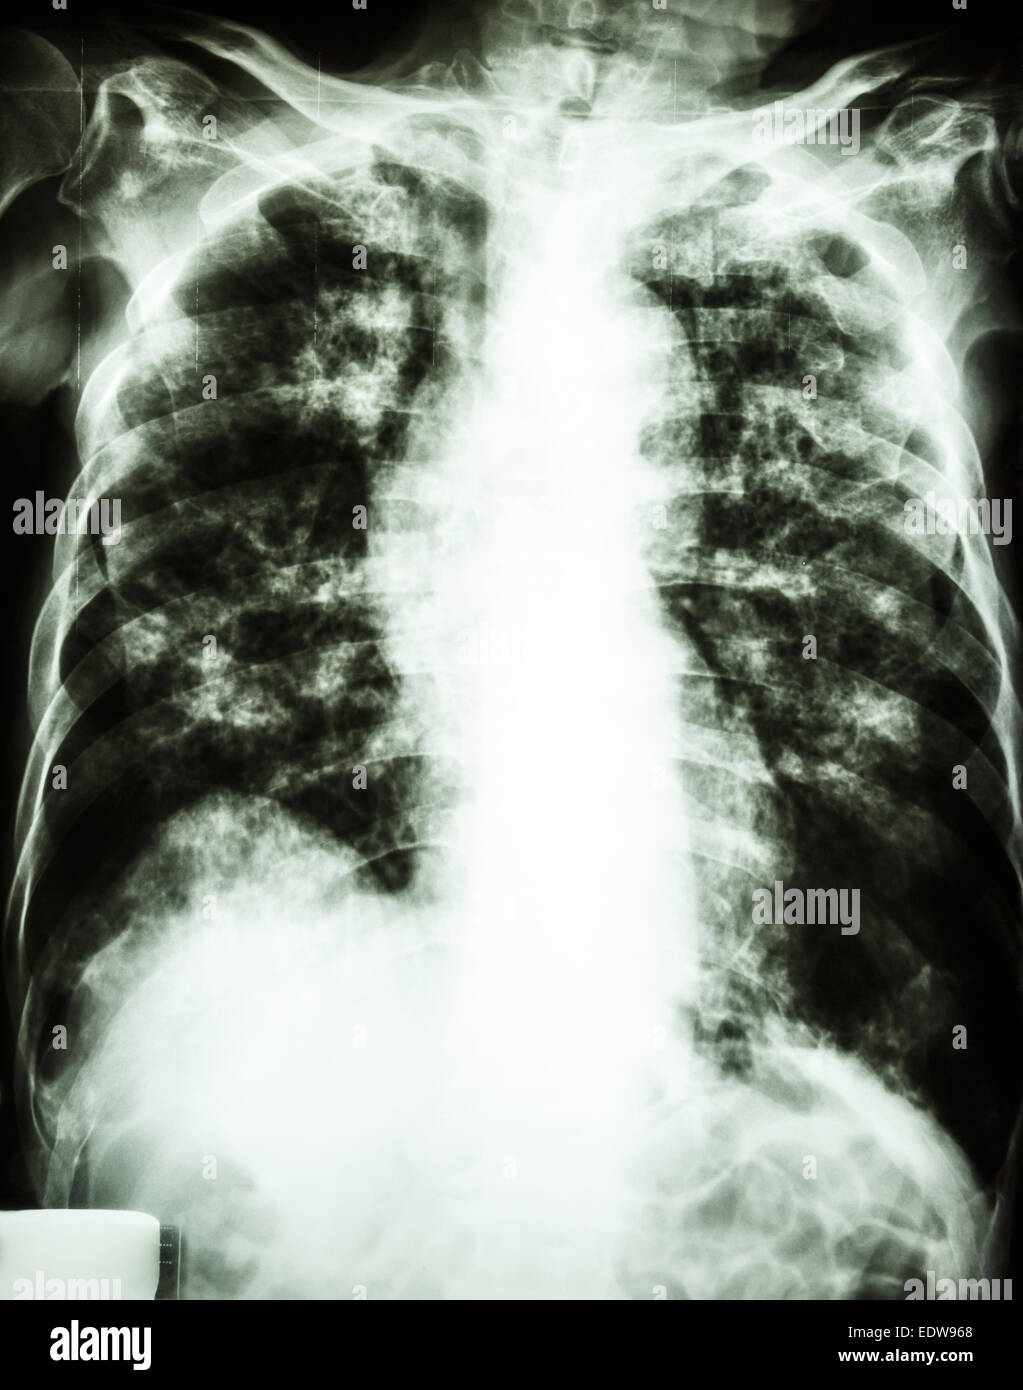

film chest xray show interstitial infiltrate and alveolar infiltrate Infiltrate Meaning Chest X Ray lung infiltrates refer to substances, such as fluid or cells, that fill the lung, appearing denser on medical imaging. persistent pulmonary infiltrate results when a substance denser than air (e.g., pus, edema, blood, surfactant,. Infiltrate Meaning Chest X Ray.

Chest Xray showing diffuse infiltrates involving bilateral lung Infiltrate Meaning Chest X Ray lung infiltrates refer to substances, such as fluid or cells, that fill the lung, appearing denser on medical imaging. persistent pulmonary infiltrate results when a substance denser than air (e.g., pus, edema, blood, surfactant,. Infiltrate Meaning Chest X Ray.